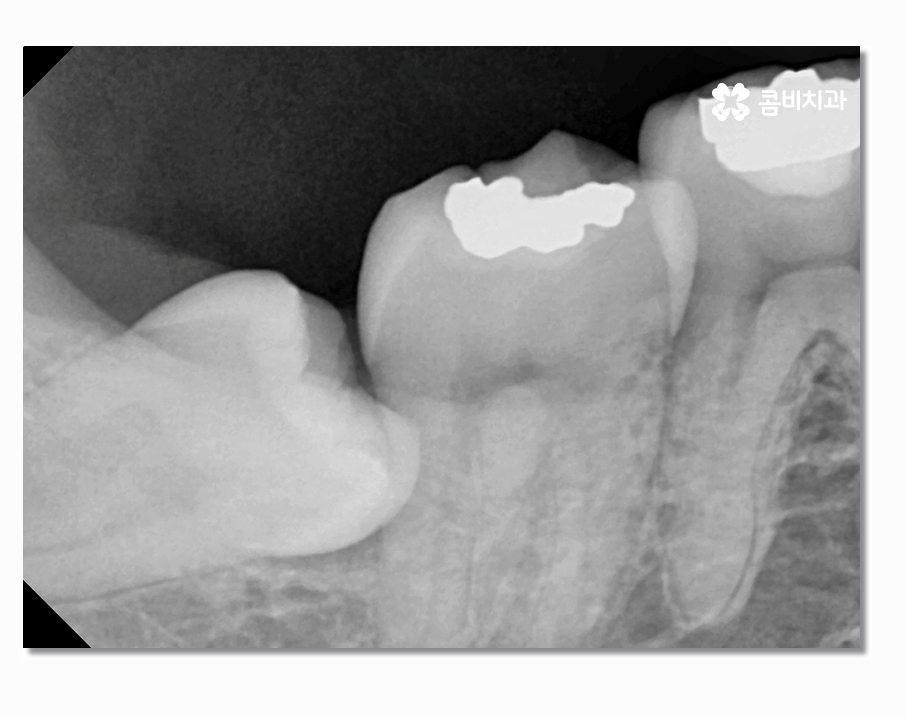

부분매복사랑니의 경우 치아가 반쯤만 잇몸 위에 맹출 되어 있어서

충치 및 잇몸질환을 일으키기도 하지만 누워서 자라는 형태인

경우도 많은데 이경우 어금니 사이에 충치를 발생시키거나

어금니를 녹게 만드는 경우도 있기 때문에 어금니 손상을 방지하기

위해서라도 발치를 서둘러야 하는 경우가 있어요

사랑니는 겉으로 보이는 것과 X Ray로 살펴보는 것이

큰 차이가 있으며 사랑니의 위치와 맹출 형태, 크기 등에 따라서

발치의 과정부터 시술 난이도의 차이가 있기 때문에

발치를 하기 좋은 시기부터 회복까지 고려하여 시술에 대한

다양한 케이스를 겪어보고 풍부한 임상 경험 및 실력을

갖춘 의료진에게 시술을 받는 것이 바람직하다고 할 수 있어요.